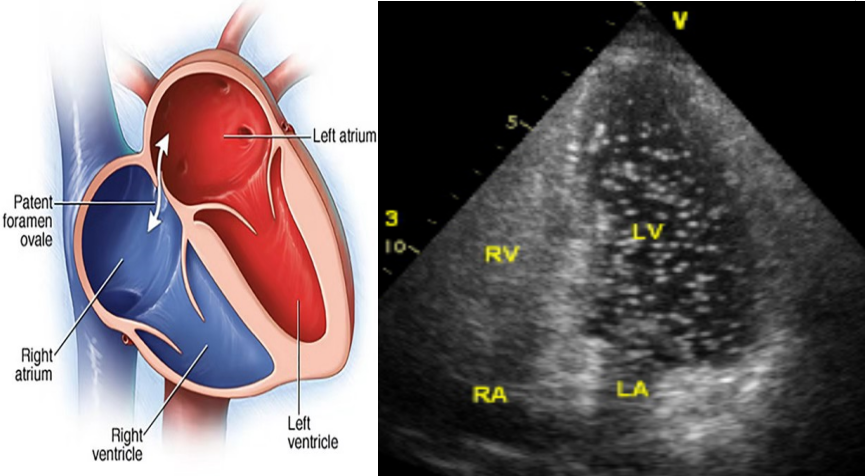

右心声学造影又称发泡实验,是一项简便易行的超声心动图检查方法。一般通过静脉注入造影剂,使右心系统显影,由于造影剂微泡直径较大(>10um),不能通过肺毛细血管网,所以正常不能进入左心系统。但是,如果左右心系统存在异常通道,造影剂通过异常通道进入左心系统,左心腔内也同时出现了微气泡显影,则提示右心声学造影阳性,并以此来协助诊断卵圆孔未闭、房间隔缺损、肺动静脉瘘、永存左上腔静脉等疾病。

(图示:房水平存在大量的右向左分流)